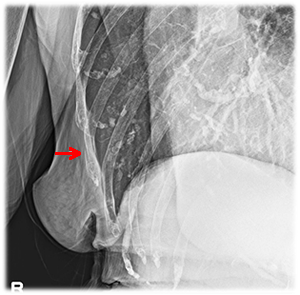

胸部レントゲン写真で、気胸・血胸の有無や重症度を評価しています。

左第9,10,11肋骨骨折

血気胸のリスクあり。